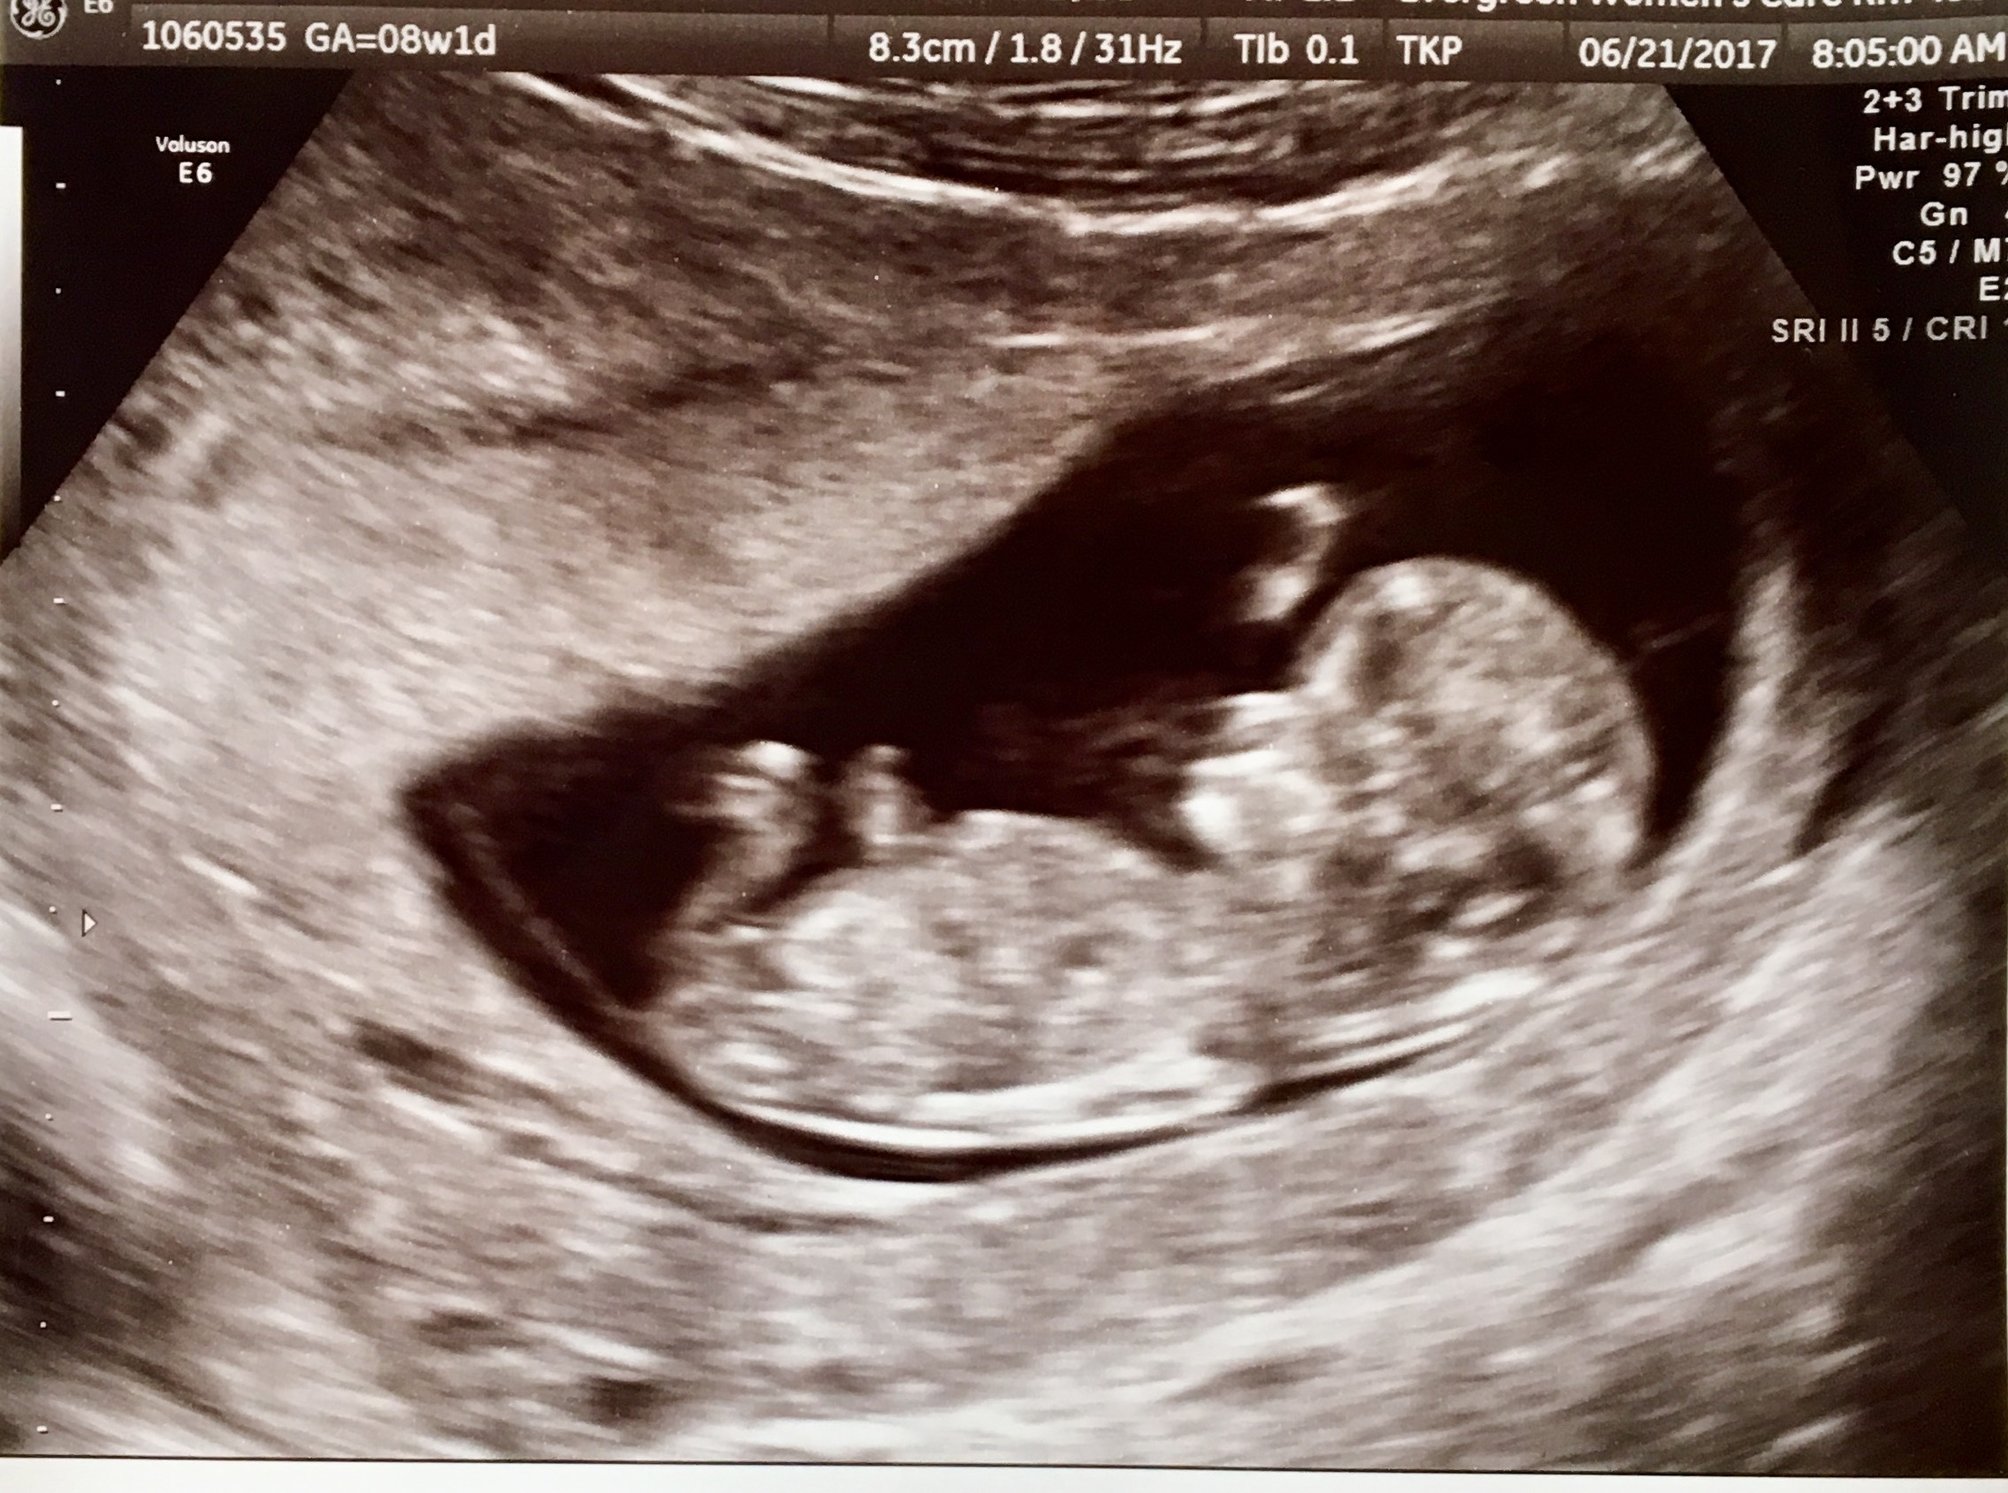

I went to my new OB (my regular gynecologist doesn't deliver babies) and had my second prenatal visit, so we got to hear the heart beat this time! I'm at 8 weeks 4 days... they keep going back and forth with my due date being January 27/28, but I know the baby will come when it feels like it! It was nice to get some more images of baby to show my father-in-law. He has pancreatic cancer and has about 6 weeks left with us.